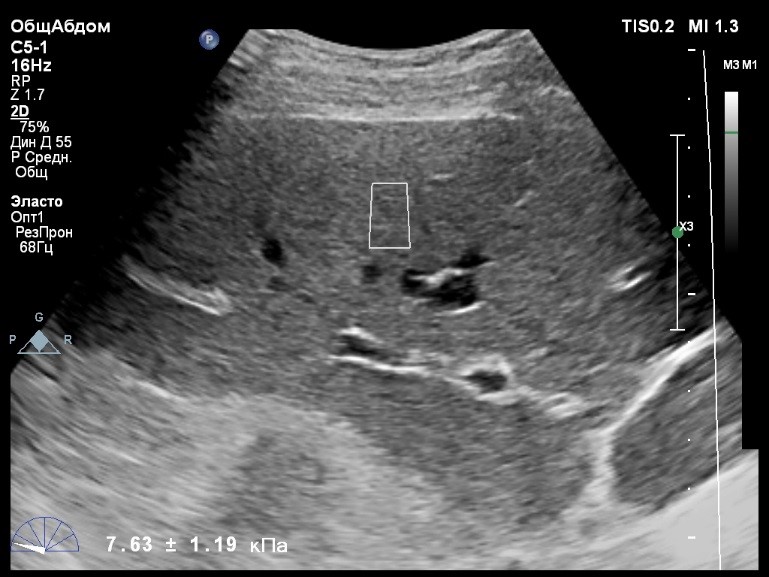

Пациент обратился к доктору с направлением на исследование степени жесткости печени в июне 2017 года. Из истории болезни, пациент страдает Гепатитом С с 2015 года. Лечение не получал. В апреле 2016 года, с помощью транзиентной эластографии была установлена медиана жесткости печени 5,8 kPA (4,4-7,7). На момент настоящего исследования, пациент не принимал пищу на протяжении 4 часов, АСТ, АЛТ не превышают патологических значений. Для оценки жесткости была выбрана технология компании Philips ElastPQ (точечная эластография) и прибор компании Philips Epiq 7 Исследование было проведено в соответствии с клиническими рекомендациями для ультразвуковых приборов компании Philips. В результате исследования были получены следующие результаты:

| 1 [4.94] kPa | 2 [7.09] kPa | 3 [7.13] kPa |

| 4 [4.74] kPa | 5 [5.17] kPa | 6 [7.78] kPa |

| 7 [6.19] kPa | 8 [7.63] kPa | 9 [4.64] kPa |

| 10 [6.18] kPa | 11 [4.49] kPa | 12 [4.54] kPa |

| 13 [6.08] kPa | | |

Стандартное Отклонение [1.17] kPa Медиана Жесткости [6.08] kPa Фактор Качества IQR/Med 9%

Зона интереса расположена на более чем на один сантиметр глубже капсулы, параллельно ходу луча, в середине изображения, в участке печени лишенном артефактов.

Капсула видна как белая линия перпендикулярная ходу ультразвукового луча, исследования производятся приблизительно в одном и том же сегменте печени.

Для интерпретации полученных клинических данных были использованы Рекомендации по проведению эластографии сдвиговой волной для оценки жесткости печени при использовании ультразвуковых аппаратов компании Филипс с примером протокола. Анамнез основного заболевания пациента достаточно короткий и показатели жесткости печени, полученные в 2016 свидетельствуют об отсутствии значимых фиброзных изменений. Однако, в течении всего времени пациент не получал специфического лечения. Данный факт является показанием для динамического наблюдения и оценки жесткости печени. Подготовка пациента соответствовала проводимому исследованию. Представленные слайды проведенного исследования свидетельствуют о правильном техническом исполнении проб, что позволяет заключиться о достоверности полученных измерений. Таким образом, учитывая полученную медиану жесткости на уровне 6.08 кРа (4.49 – 7.78 kPa) и уровень стандартных отклонений не превышающих 30%, полагаю, что уровень степени фиброза соответствует стадии F 0-1. Заведующий отделением УЗД МЦ «Асклепий», Глушенко Д. Е.